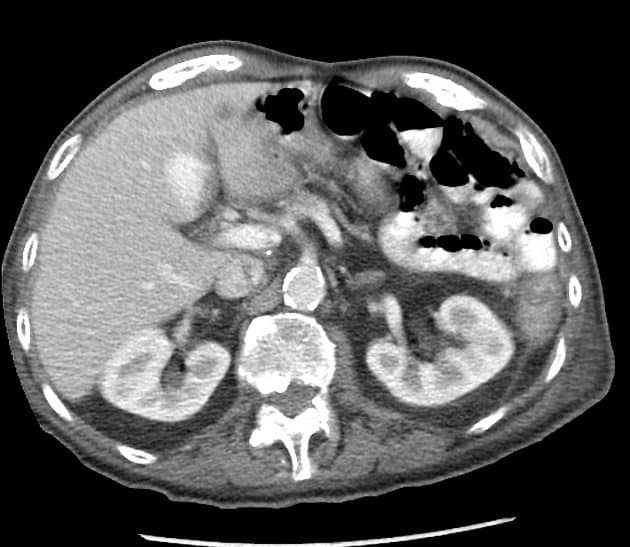

Phình TM cửa

» Thông tin: Nam giới – 90 tuổi.

» Lâm sàng: Kiểm tra sức khỏe.